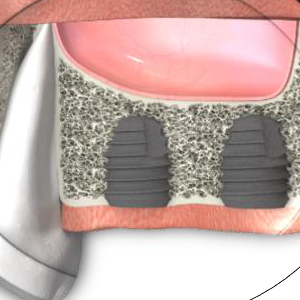

Лечение с импланти в страничния участък на долната челюст - триизмерна схема, която е предоставена на нашия екип от компанията Neobiotech. Статистически това се налага също много често - първите молари са едни от първите зъби, които се налага да се екстрахират по различни приини. От една страна, тези зъби поникват рано, когато не са достатъчно минерализирани и бързи се засягат от кариес. Много локализирани форми на пародонтит също се развиват първоначално при шестите зъби - което също води до загуба на зъба с последваща необходимост от протезиране. Всички тези увреждания засягат както долната, така и горната челюст - което изисква и съответното адекватно лечение на дефекта. При мандибулата е налице съдово - нервен сноп, който се разполага във вътрешността на костта и създава затруднения. Докато повдигането на пода на горночелюстния синус е технически лесно, транспозицията на долния алвеоларен нерв и артерия са доста по-трудни и изискват продължителен, неприятен и болезнен заздравителен процес. Интра- и постоперативните рискове при подобни интервенции са освен това доста по-големи.